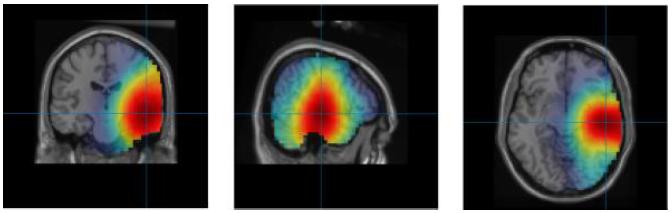

CREDIT: Yunlong ShaoCould artificial intelligence help solve the mental health crisis? What if an algorithm allowed neurologists to know the area affected by a brain seizure?

These are just two of the questions that Maryam Ravan, Ph.D., assistant professor of electrical and computer engineering, aims to address. Working on two separate studies, she proposes the use of cutting-edge algorithms and techniques that could provide noninvasive solutions for clinicians to treat neurological and psychiatric conditions more effectively.

Normal brain activity, including mood and thinking processes, relies on a balance of fast and slow brain waves. Imbalanced brain wave activity is associated with neurological issues such as epilepsy and psychiatric conditions like bipolar disorder and major depressive disorder.

One technique clinicians use to detect brain wave imbalances is electroencephalography (EEG). This diagnostic test uses sensors to measure the electrical activity on a patient’s scalp, which is representative of the brain wave activity taking place underneath. Brain wave data collected through an EEG holds valuable information regarding an individual’s neurological and mental health. Existing software models that process EEG brain wave data use a mathematical technique called exact low-resolution brain electromagnetic tomography (eLORETA).

In collaboration with McMaster University psychiatrist Gary M. Hasey, M.D., Ravan co-authored two studies that leverage machine learning, a form of artificial intelligence (AI), to improve the treatment of mental health conditions.

In one study, Ravan helped develop a machine learning algorithm to analyze patients’ brain waves and categorize their patterns as biomarkers for bipolar disorder or major depressive disorder.

The researchers pose that, given its abilities, machine learning could be useful in analyzing a patient’s EEG results and determining whether a patient is experiencing bipolar disorder or major depressive disorder. With Ravan’s expertise, the team developed a new algorithm called ReLORETA, which accounts for multiple variables known to impact brain source estimates, including head geometry and misaligned brain electrodes, among other factors.

“The accuracy of our algorithm, which was derived from a large sample of patients, successfully distinguished bipolar disorder from major depressive disorder more accurately than

the existing methods available to clinicians,” says Ravan. “This suggests that our method may hold significant promise as a clinical tool.”